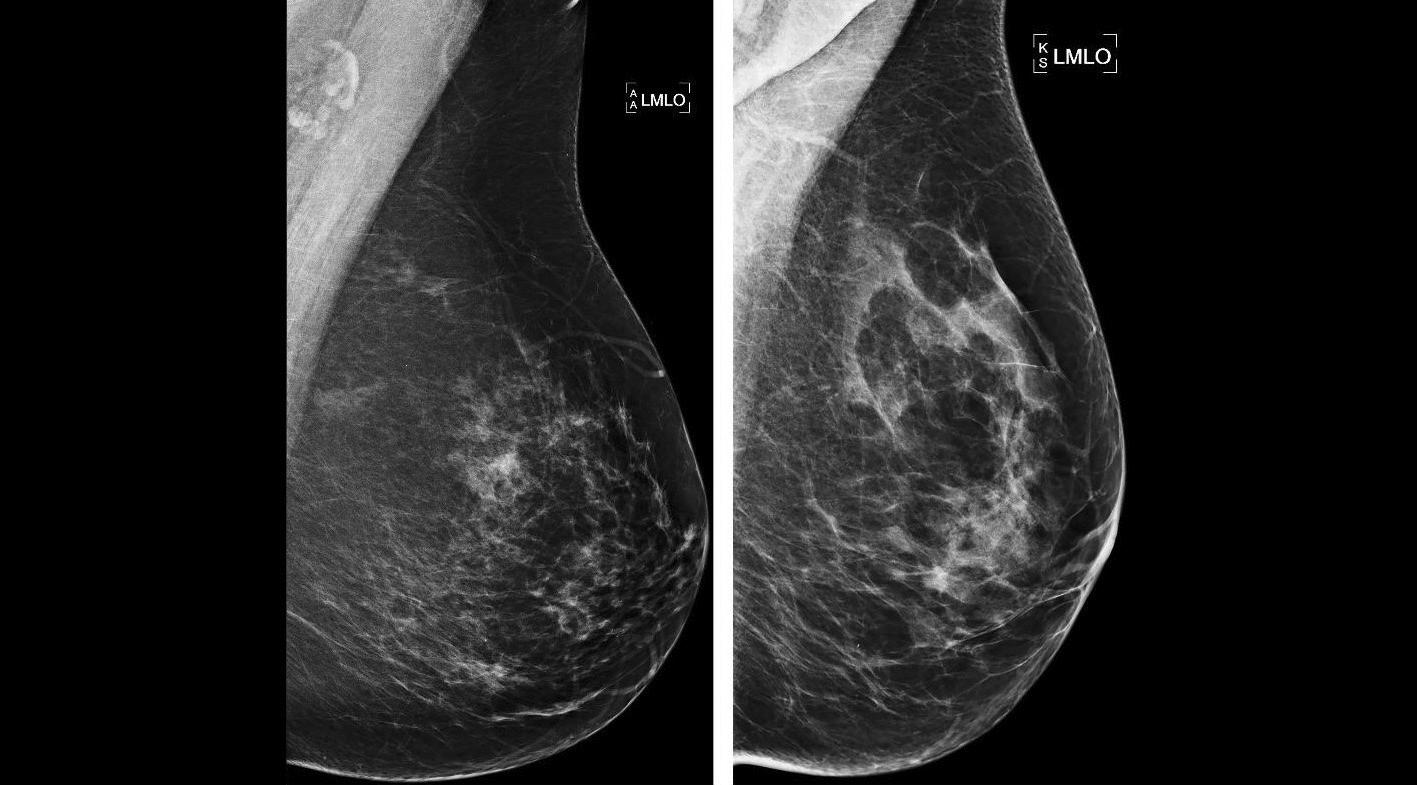

Quels biais entrent en jeu dans l’interprétation des mammographies et quelles méthodes appliquer pour s’en prémunir ? Pour répondre à cette question, des chercheurs ont réalisé une revue pédagogique publiée dans Insights into Imaging au mois de janvier [1], où ils décrivent plusieurs exemples illustratifs et des stratégies pour réduire les erreurs d’interprétation.

« Parmi les facteurs contribuant aux erreurs en imagerie mammaire, on peut citer les biais cognitifs liés au lecteur, les caractéristiques des lésions, les variables spécifiques à la patiente et les limites techniques, indiquent les auteurs. Pour relever ces défis, les stratégies clés comprennent la reconnaissance structurée des erreurs, les processus d'évaluation par les pairs et les programmes rigoureux d'assurance qualité. » Au chapitre des biais liés aux lecteurs, les auteurs citent notamment le facteur de « satisfaction of search », les biais de confirmation, les biais d’inattention, les bia